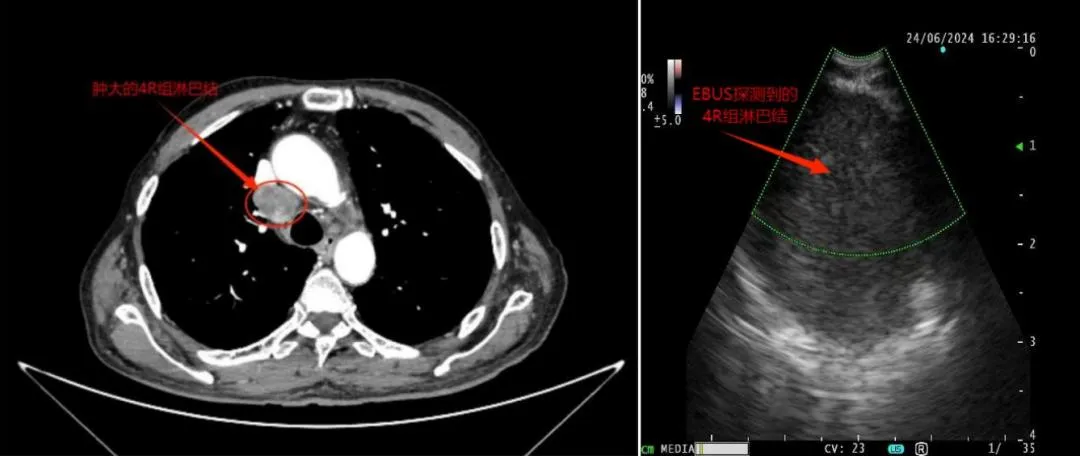

超声支气管镜引导下的经支气管针吸活检术(EBUS-TBNA)正在成为肺部疾病诊断的“新利器”。这项技术通过在支气管镜前端安装超声探头,结合专用的吸引活检针,在实时超声引导下进行针吸活检。搭载的电子凸阵扫描的彩色能量多普勒还能帮助确认血管位置,防止误穿血管,大大提高了传统TBNA的安全性和准确性。

EBUS-TBNA的应用范围不仅限于肺癌诊断。它还可以用于诊断肺内肿瘤、不明原因的肺门和纵隔淋巴结肿大以及纵隔肿瘤等。随着技术的不断进步和临床经验的积累,EBUS-TBNA在肺部疾病诊断中的应用前景将更加广阔。